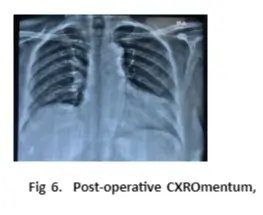

The patient was posted for a diagnostic laparoscopy with the repair of diaphragmatic hernia. During surgery, the contents of the hernia sac being transverse colon, stomach, and omentum were reduced in the abdominal cavity. The falciform ligament was divided. The defect in the diaphragm was present anterior to the esophagus just behind the sternum suggestive of Morgagni hernia measuring 10 x 6 cm. The hernia defect was closed using intermittent sutures of prolene 1-0. The repaired diaphragm was further reinforced with prolene mesh. The postoperative period of the patient was uneventful, and she was discharged on the third day after surgery.